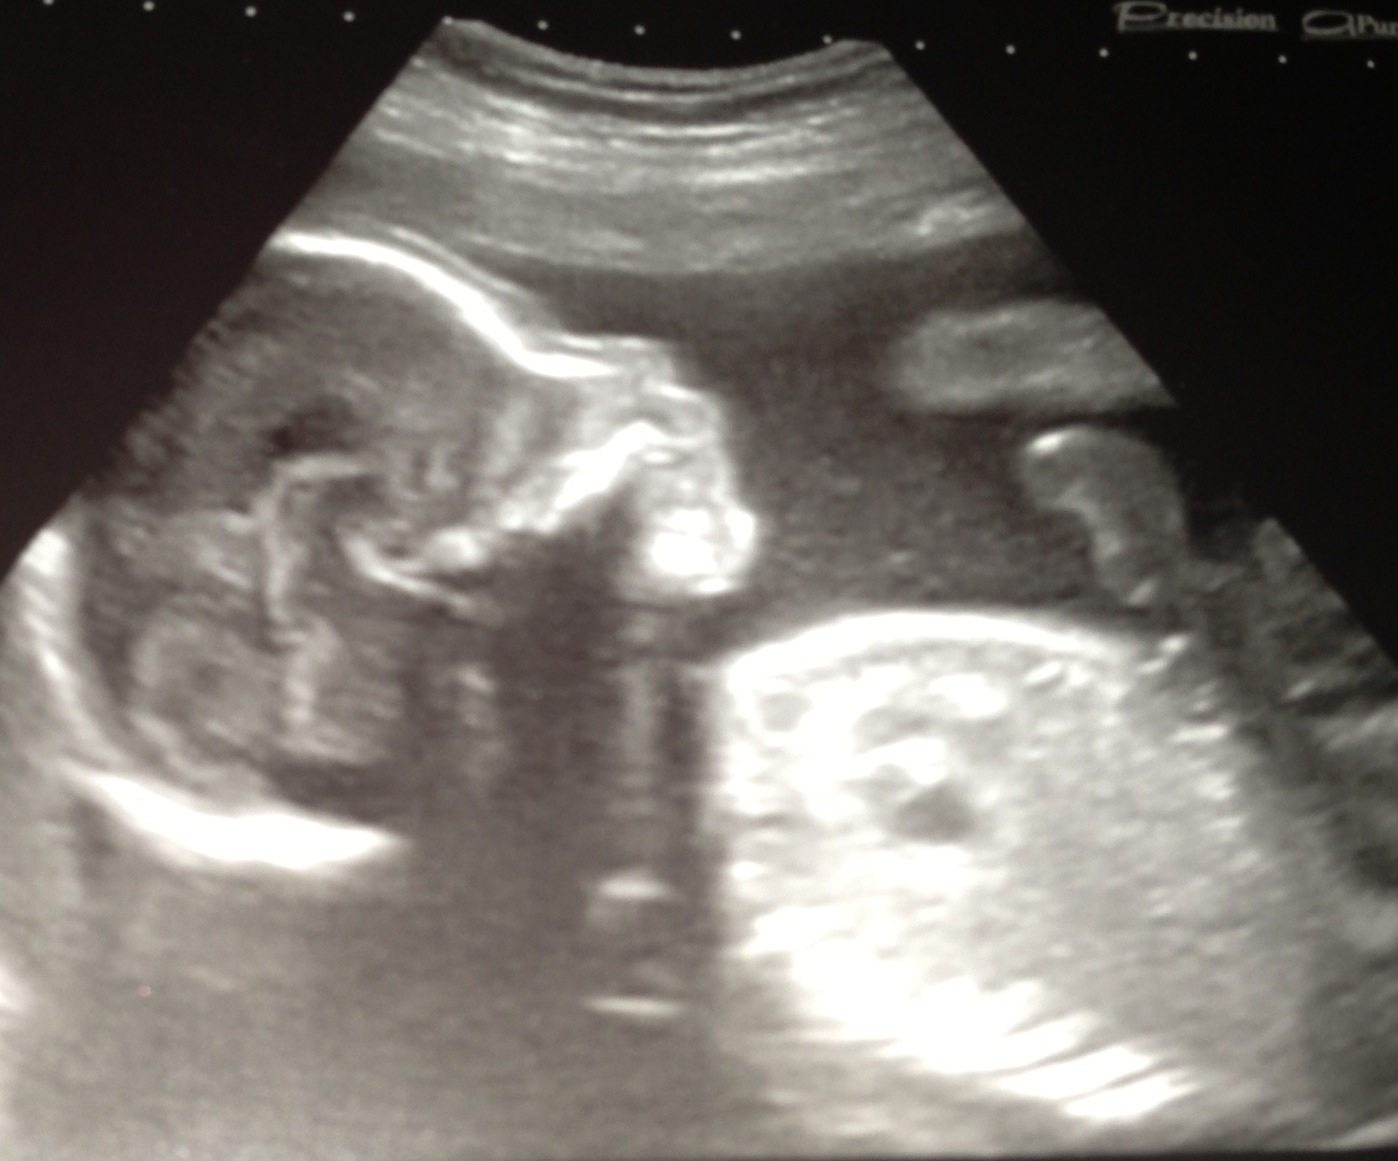

I posted this photo on another thread...just wondered if anyone could predict the sex of my little one. I have a feeling girl and I find out on Wednesday...any ideas? Thanks :-)Attachment 11824

I wonder which stripe is the nub? And what are those other stripes? Because depending on the stripe, I guess boy (top one) or girl (botton line) lol.

I think there may be a bit of cord happening down there.....but I think the bottom line may be the nub so I will ever so slightly guess girl....but I'm not overly confident!

It is a little boy!! My instinct was wrong...it always is hehe! Need to think of a name now! I only thought of a girls name!! Thanks everyone xx